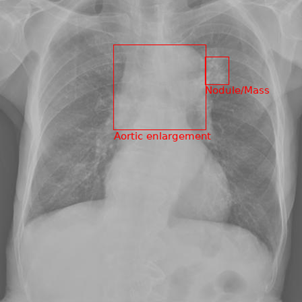

As a qualitative result, Figures 3-5 illustrates an input chest X-ray image along with the disease classification and localization generated by the proposed method using the default prompt with MiniGPT-Med initialization trained with a batch size of 10.

Refer to caption

(a) Other diseases (Test Label)

(b) Other diseases (Model Output)

Figure 3. Qualitative comparison between test labels and model output for other diseases.

Qualitatively, when looking at the example in Figure 3, it has both the test label and the model output for diagnosis as the same, the diagnosis being ’Other Disease’. The model also does a good job of getting some of the correct local labels. There is an aortic enlargement in both the reference and model output, but just barely overlap with one another. Instead of predicting calcification, the model predicts cardiomegaly. Overall, this example comparison is a strong showing for what the model is capable of albeit on a simple (only two abnormalities) data point.